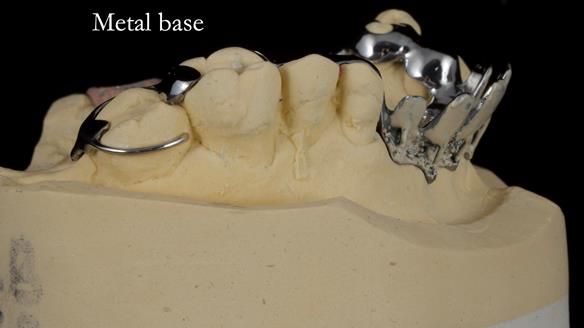

Keith’s case was one of the most challenging and rewarding cases I’ve treated this year. This 64 year old man presented with ill-fitting acrylic partial dentures that lacked stability, retention, and aesthetics. They constantly broke. He had lost the upper front teeth in a road traffic accident in his early 20s. The unopposed teeth had erupted, taking up space. After careful planning, we made a durable, metal-based upper partial denture/splint to address his dental concerns. He loved the outcome.

1. Denture design: A custom cobalt-chromium framework was Scandinavian-designed to maximise stability, protect the remaining teeth, and allow for future additions if needed.

Keith’s denture incorporated a Duracetal shell clasp on upper right first premolar (Myerson), which are designed to be virtually visible, providing a more aesthetic solution while enhancing patient comfort. The Scandinavian-inspired approach, based in modern removable prosthodontic techniques, ensured the denture was not only durable but also visually pleasing. Additionally, the design was carefully planned to allow for future modifications, ensuring that if Keith loses additional teeth, the denture can be adapted rather than replaced entirely.